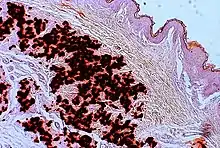

Histopathology of PXE-like papillary dermal elastolysis: Loss of elastic fibers in the papillary dermis and abnormal pattern in the reticular dermis (arrow)[28]

PXE-like papillary dermal elastolysisLM: Selective elastic tissue elimination in the papillary dermis and presence of melanophages